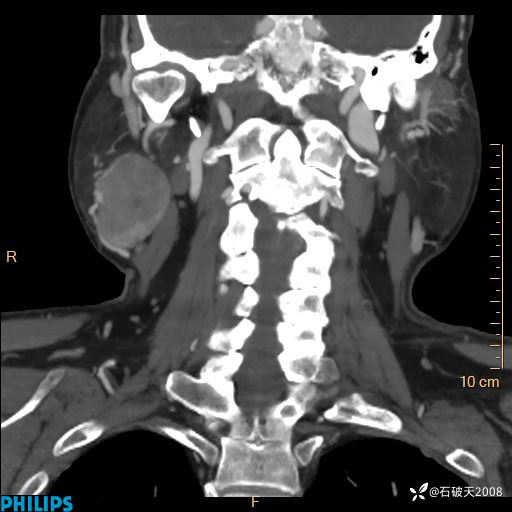

MIP